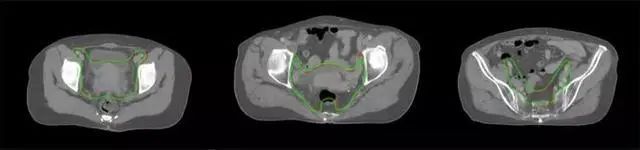

四、放射治療智能勾畫軟件

放射治療,簡稱放療,是治療腫瘤主要手段之一,利用放射線破壞照射區(qū)(靶區(qū))的細(xì)胞,使腫瘤細(xì)胞停止分裂直至死亡,醫(yī)生通常把放射治療形象的比喻為“打靶”,放療前精準(zhǔn)勾畫腫瘤靶區(qū)范圍是腫瘤放射治療的關(guān)鍵步驟。傳統(tǒng)的靶區(qū)勾畫醫(yī)生會根據(jù)患者多張CT、MRI影像片憑借經(jīng)驗(yàn)進(jìn)行,比較耗時,治療的病人數(shù)量也有限,且靶區(qū)勾畫缺少行業(yè)統(tǒng)一的規(guī)范和標(biāo)準(zhǔn),無法達(dá)到同質(zhì)化,勾畫精確度不理想。

技術(shù)原理

基于深度學(xué)習(xí)人工智能的放療靶區(qū)智能勾畫技術(shù)和自動計劃技術(shù),基于全面的市場調(diào)研和臨床專業(yè)意見,采用獨(dú)創(chuàng)的基于小樣本量的人工智能算法,實(shí)現(xiàn)放療靶區(qū)和危及器官的快速全自動勾畫。

產(chǎn)品優(yōu)勢

縮短至幾分鐘內(nèi)便可完成,大幅提升了放療效率,且人工智能平臺完成的靶區(qū)勾畫可基本滿足臨床醫(yī)生需求,專家只需審核時細(xì)微調(diào)整,可顯著提高靶區(qū)勾畫的規(guī)范化及精準(zhǔn)度,讓放療智能化,標(biāo)準(zhǔn)化??筛采w食管癌、鼻咽癌、直腸癌、宮頸癌、肺癌等多種病種。